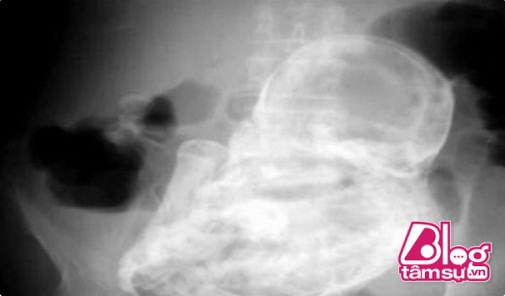

Bà lão không dám tin vào mắt mình khi nhìn tấm X-quang ghi lại chiếc bụng bầu to phình nhiều ngày của mình.

Theo những hình ảnh được chụp lại bên trong, chiếc bụng của bà lão có kích thước bất thường như vậy là do nó chứa một bào thai đã chết. Bào thai này được dự đoán đã tồn tại trong bụng của người bà lão 38 năm. Đây chính là tình trạng thai lưu mà hàng triệu người phụ nữ rất sợ hãi. Vì không kiểm tra và phát hiện kịp thời nên bào thai này đã bị chuyển biến trong cơ thể người phụ nữ.